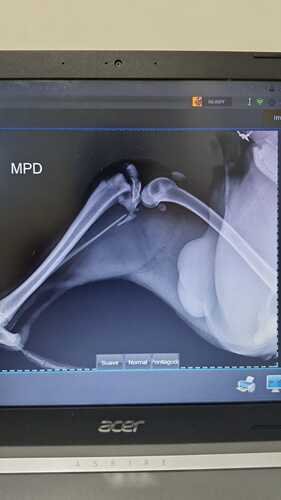

Nós, Rafael e Isabela, não pensamos duas vezes e o levamos imediatamente ao veterinário Dra.Vet. O diagnóstico foi devastador: Pingo quebrou as duas patinhas traseiras e precisa de uma cirurgia urgente para voltar a andar. A boa notícia? Ele tem grandes chances de recuperação, pois, apesar do acidente, nenhum órgão interno foi afetado!